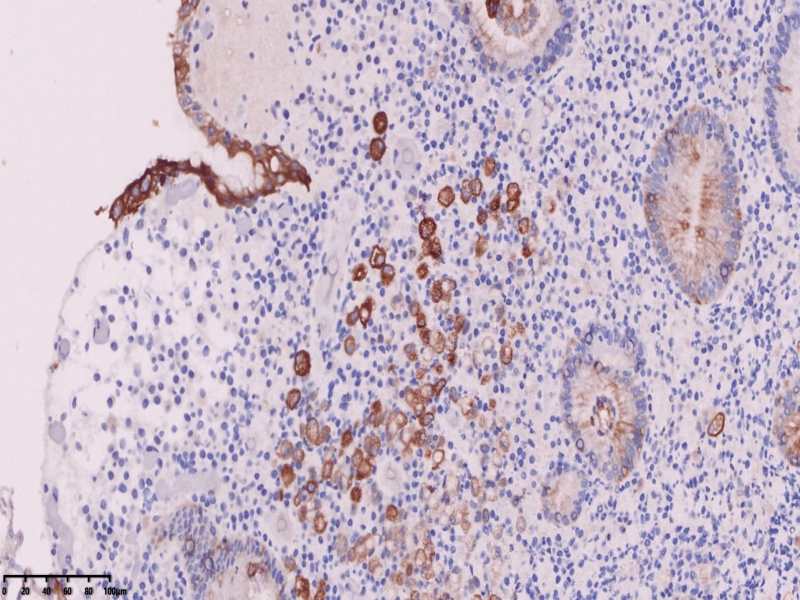

免疫组化标记后异型上皮细胞更显著。

CKpan

ck7